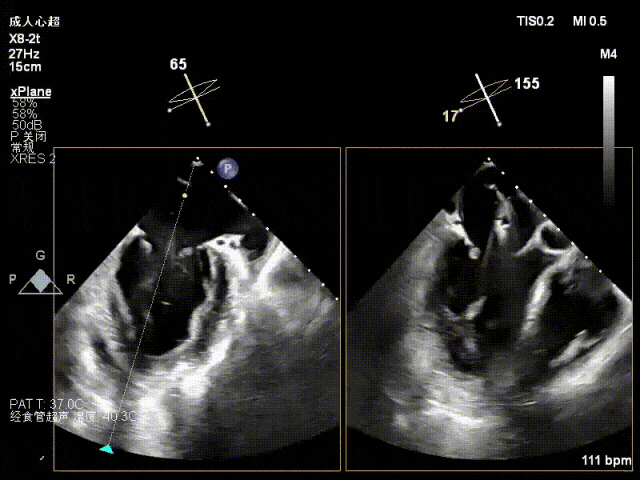

术中超声要点

术前术后对比图

术前

术后

术后,出院检查报告显示夹子位置固定,二尖瓣、三尖瓣及主动脉轻微反流,左房增大,左室内径正常上限,EF值正常下限(WMSI 1分)。